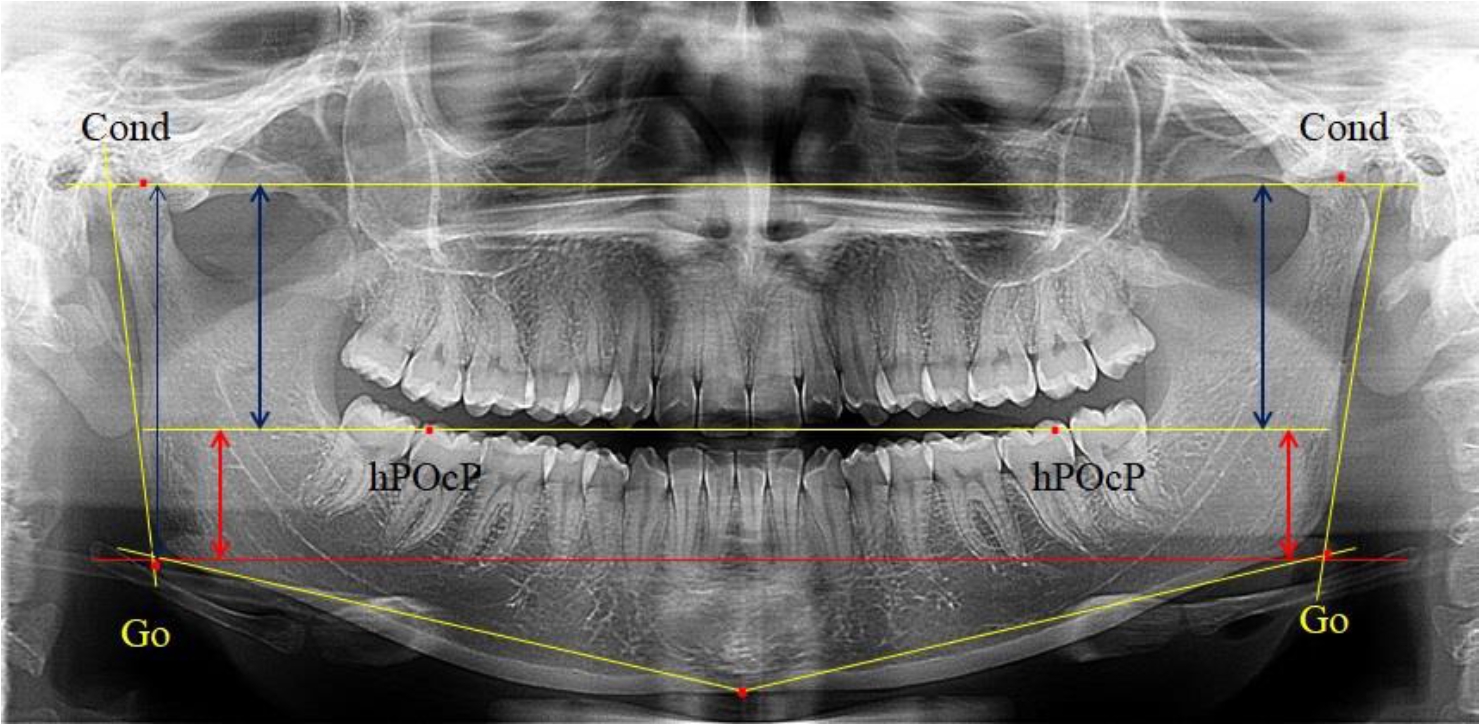

На боковых телерентгенограммах определяли положение верхней точки суставной головки Cond. Касательные линии к ветви и телу нижней челюсти пересекались в точке, которую в клинической практике обозначают как точка угла нижней челюсти или точка гонион Go. Точкой hPOcP обозначали дистальный бугорок нижнего второго моляра вблизи окклюзионного контура коронки, через нее от межрезцовой точки проводили окклюзионную линию, ее продолжали до задней части ветви челюсти. Высоту ветви измеряли как расстояние от угла нижней челюсти до вершины суставной головки Go-Cond. Общую высоту ветви условно делили на 2 части, ее границей служила окклюзионная линия. Верхнюю часть обозначали как окклюзионно-суставная, а нижнюю – как окклюзионно-гониональная.

На ортопантомограмме использовали аналогичные суставные точки Cond на каждой стороне, их соединяли между собой суставной линией Cond-Cond.

Касательная к ветви нижней челюсти соединяла выступающие точку. При построении касательной к телу челюсти проводили в обе стороны линии от точки Gn, расположенной в нижней центральной части подбородочного симфиза, до выступающей нижней точки угла челюсти. Касательные линии при пересечении определяли конструктивную точку гонион Go. Соединение гониональных точек определяло положение гониональной линии Go-Go. При соединении окклюзионных точек hPOcP получали окклюзионную горизонталь (рис. 1). Измеряли расстояние между горизонталями в области ветвей нижней челюсти. Статистический анализ проводили в программе Microsoft Excel. Составляли вариационные ряды с последующим расчетом среднего значения, стандартного отклонения и ошибки среднего ±m. Также оценивали максимальные и минимальные значения величин. Определи относительные величины соотношения верхней и нижней частей ветви нижней челюсти.

Рис. 1. Метод измерения высоты ветви нижней челюсти на телерентгенограмме (а) и ортопантомограмме (б)

Во 2-ю подгруппу был включен 21 комплект телерентгенограмм и ортопантомограмм [или (28,38 ± 5,24) %], на которых средняя величина отношения верхней части ветви к нижней составляла 1,63 ± 0,03, что было достоверно меньше показателя, полученного по группе в среднем и в 1-й подгруппе.

Визуально параметры ветви отличались от первой группы (рис. 3).

Рис. 3. ОПТГ пациента 2-й группы с уменьшенным коэффициентом соотношения частей ветви нижней челюсти

Высота ветви составляла (62,75 ± 1,42) мм и достоверных различий по этому показателю не отмечено. Максимальная высота была 73 мм, а минимальная – 55 мм. Высота верхней части составляла (38,81 ± 0,76) мм, что было достоверно меньше, чем у людей 1-й подгруппы.

В то же время высота нижнего отдела ветви была (23,94 ± 0,73) мм, и показатель отличался в большую сторону по сравнению с аналогичным размеров в 1-й подгруппе.